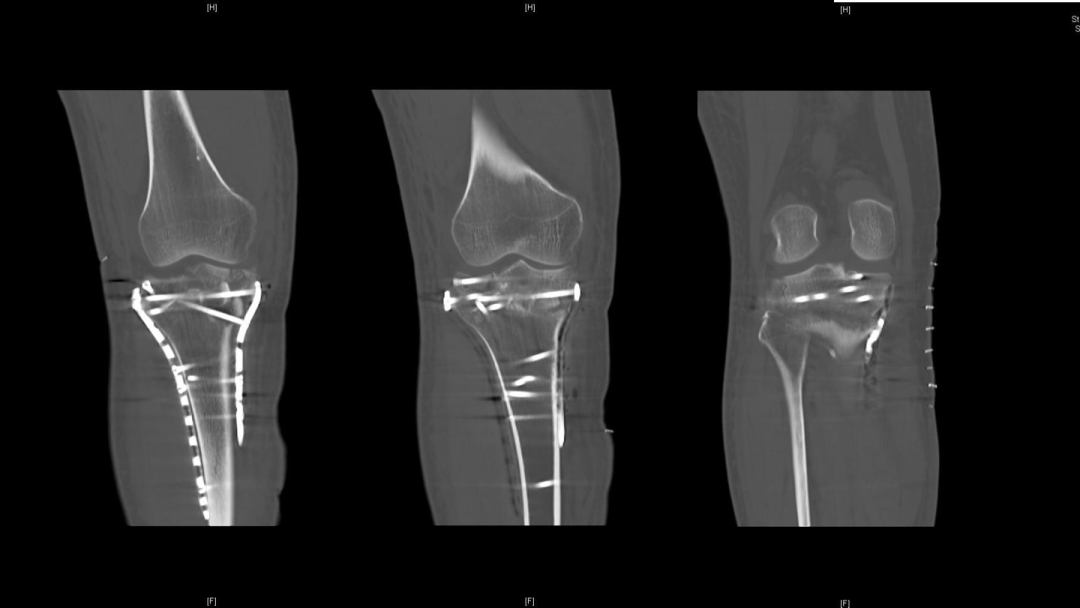

过伸型胫骨平台骨折的治疗,超详细解析!